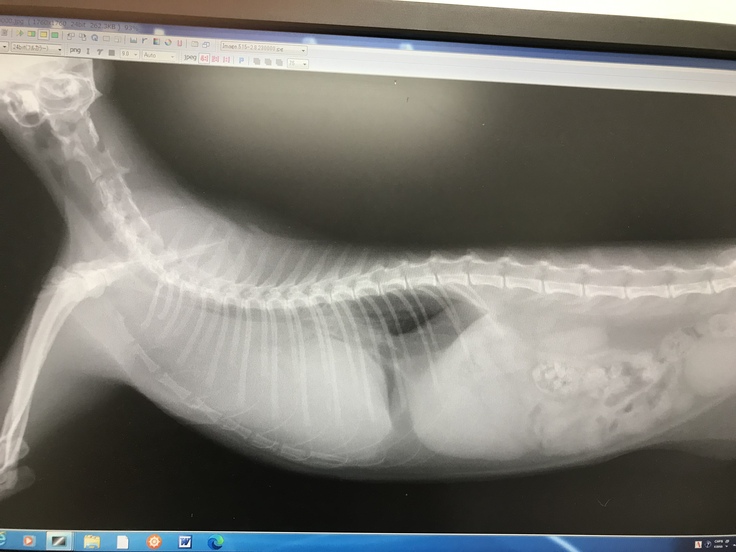

レントゲンでの腫瘍が目に見えて小さくなっており、本当に嬉しかったです。でも、まだまだ換気ができる肺は小さく、予断を許さない状況でした。

画像は病院様に記載許可を頂いています。

この画像でもすごく良くなっています。抗がん剤の前は、黒い部分(換気できる肺)はまったくありませんでした。